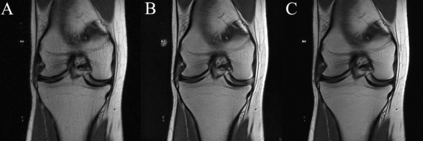

We present $\zeta$-DP, an extension of differential privacy (DP) to complex-valued functions. After introducing the complex Gaussian mechanism, whose properties we characterise in terms of $(\varepsilon, \delta)$-DP and R\'enyi-DP, we present $\zeta$-DP stochastic gradient descent ($\zeta$-DP-SGD), a variant of DP-SGD for training complex-valued neural networks. We experimentally evaluate $\zeta$-DP-SGD on three complex-valued tasks, i.e. electrocardiogram classification, speech classification and magnetic resonance imaging (MRI) reconstruction. Moreover, we provide $\zeta$-DP-SGD benchmarks for a large variety of complex-valued activation functions and on a complex-valued variant of the MNIST dataset. Our experiments demonstrate that DP training of complex-valued neural networks is possible with rigorous privacy guarantees and excellent utility.